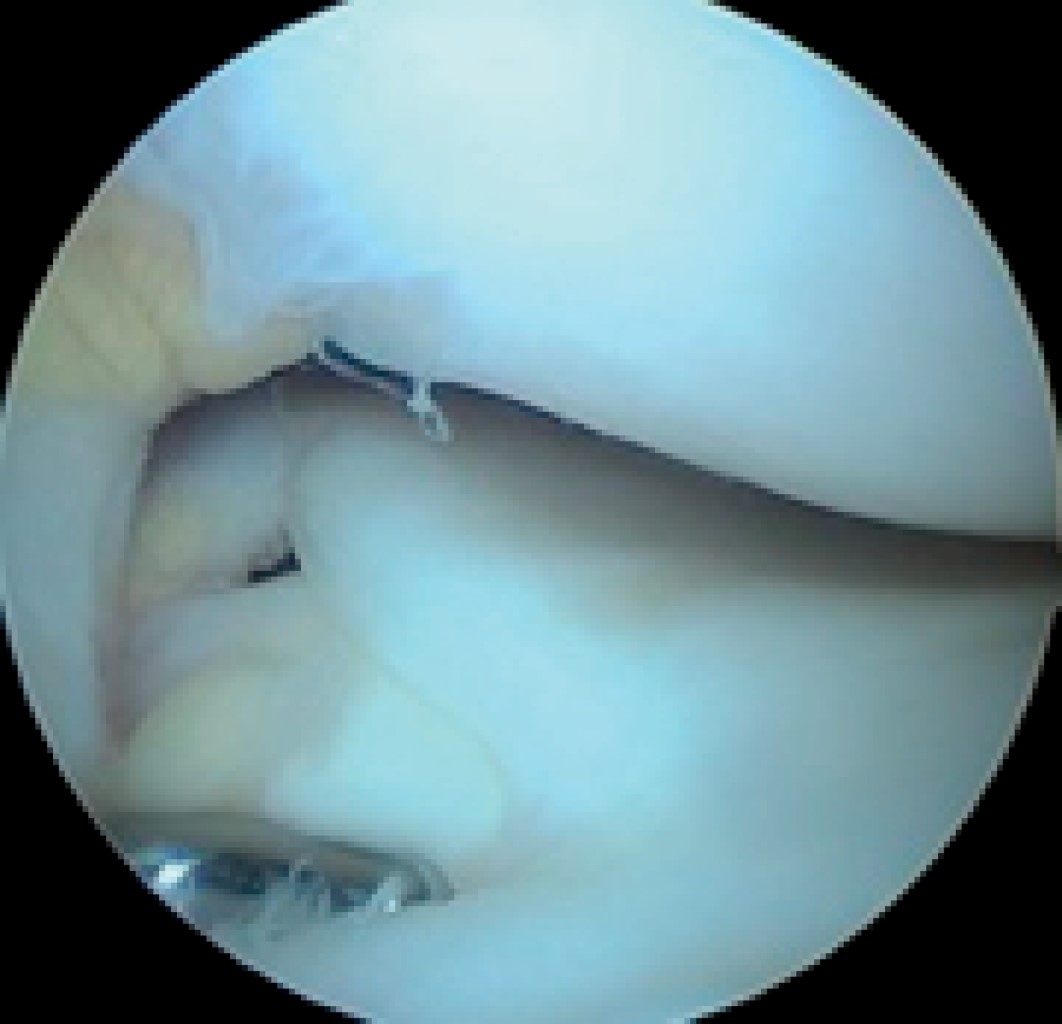

En algunas circunstancias puede ser necesaria una artroscopia para confirmar el diagnóstico, especialmente en un paciente sintomático con una variante inestable que tiene una apariencia normal en la resonancia magnética (Figura 5).72